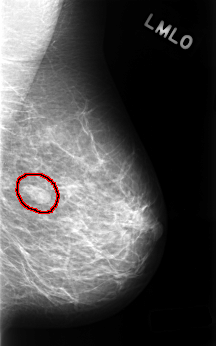

FILE: C_0489_1.LEFT_MLO.OVERLAY

TOTAL_ABNORMALITIES 1

ABNORMALITY 1

LESION_TYPE MASS SHAPE OVAL MARGINS CIRCUMSCRIBED

ASSESSMENT 3

SUBTLETY 5

PATHOLOGY BENIGN

TOTAL_OUTLINES 1

BOUNDARY